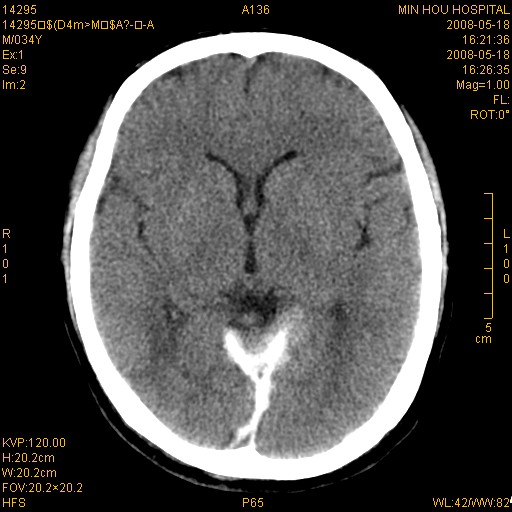

标题: CT13617:双顶叶白质水肿伴大脑镰小脑幕广泛钙化 [打印本页]

标题: CT13617:双顶叶白质水肿伴大脑镰小脑幕广泛钙化

双侧侧脑室后脚旁对称性低密度影,符合肾上腺白质营养不良(成人型)改变    小脑幕及大脑廉钙化  可考虑为生理性

支持:1、肾上腺白质营养不良.2、小脑幕、大脑镰广泛钙化。3、建议进一步检查。

硬脑膜钙化是主因,双侧顶叶白质密度减低是可能由于静脉路回流受阻所致。